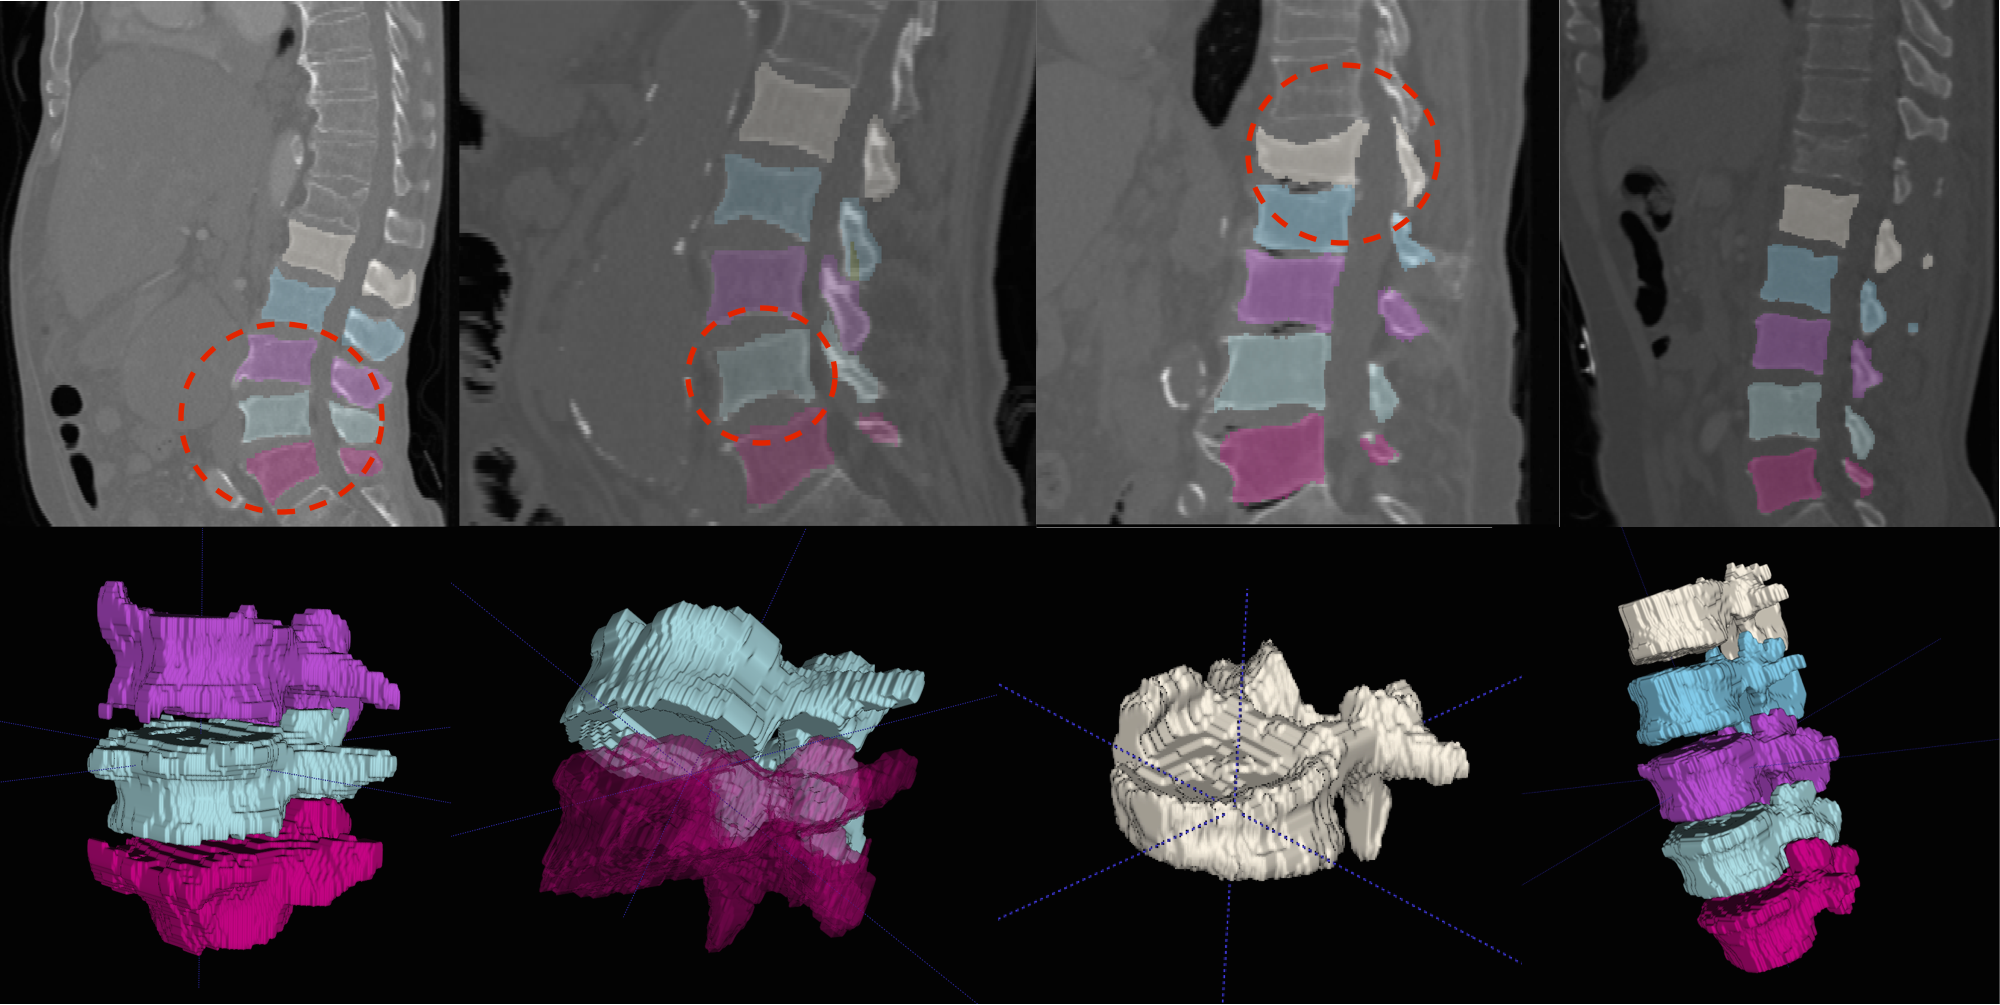

We present more results of multi-class segmentation on the test set of xVertSeg (figure 5) in addition to the results in figure 4, thereby emphasising the robustness of our approach. We also present a few aberrant segmentations analysing which could further improve our approach.